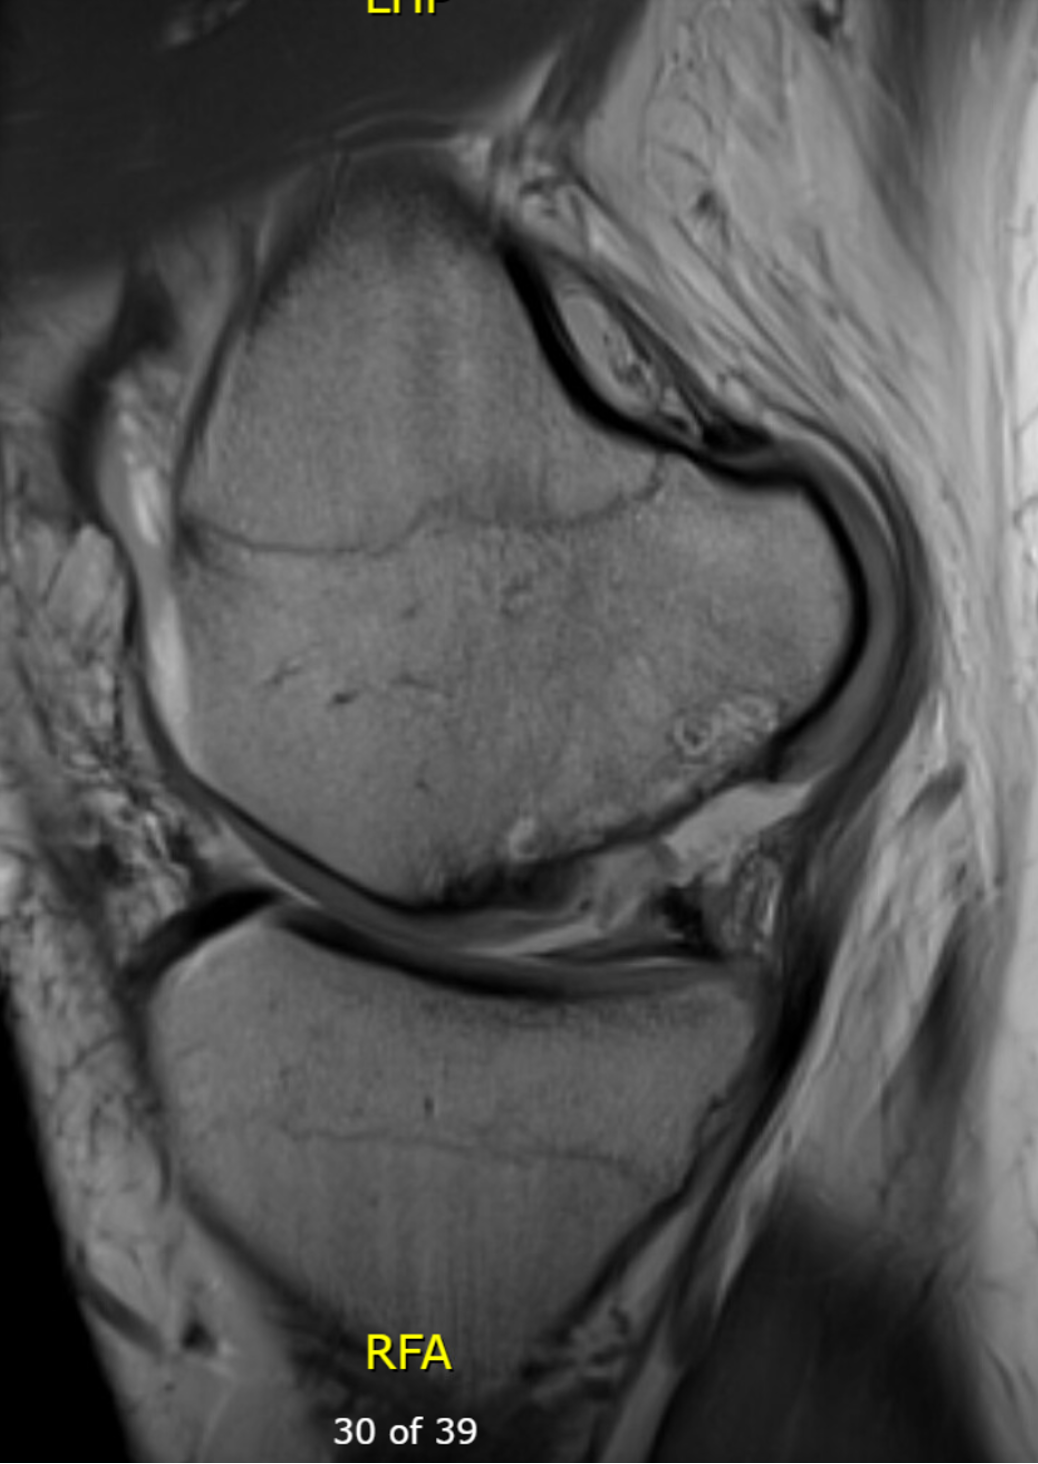

MRI

Chondral defect

Osteochondral defect